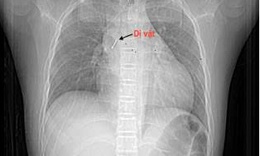

Hai bệnh viện phối hợp gắp mảnh xương cá, giúp cụ bà 84 tuổi cai máy thở

Y tế - 02/10/2025 15:54SKĐS - Mảnh xương cá mắc sâu trong phế quản khiến cụ bà 84 tuổi suy hô hấp phải thở máy. Nhờ sự phối hợp nhịp nhàng giữa hai bệnh viện, dị vật được lấy ra an toàn, giúp người bệnh hồi phục và cai máy thở.